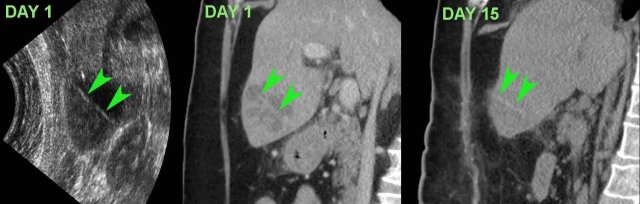

This patient presented with upper abdominal pain and a CRP of 245. US and CT revealed a slightly hyperdense, straight foreign body, probably a cocktail stick (arrowheads) .

At surgery two days later the liver abscess was evacuated, but the foreign body was not found. Afterwards  the patient did well on antibiotics.

On day 15, CT showed resolution of the abscess with the foreign body (arrowheads) still in situ. Eventually, the patient recovered with long-term antibiotic treatment.